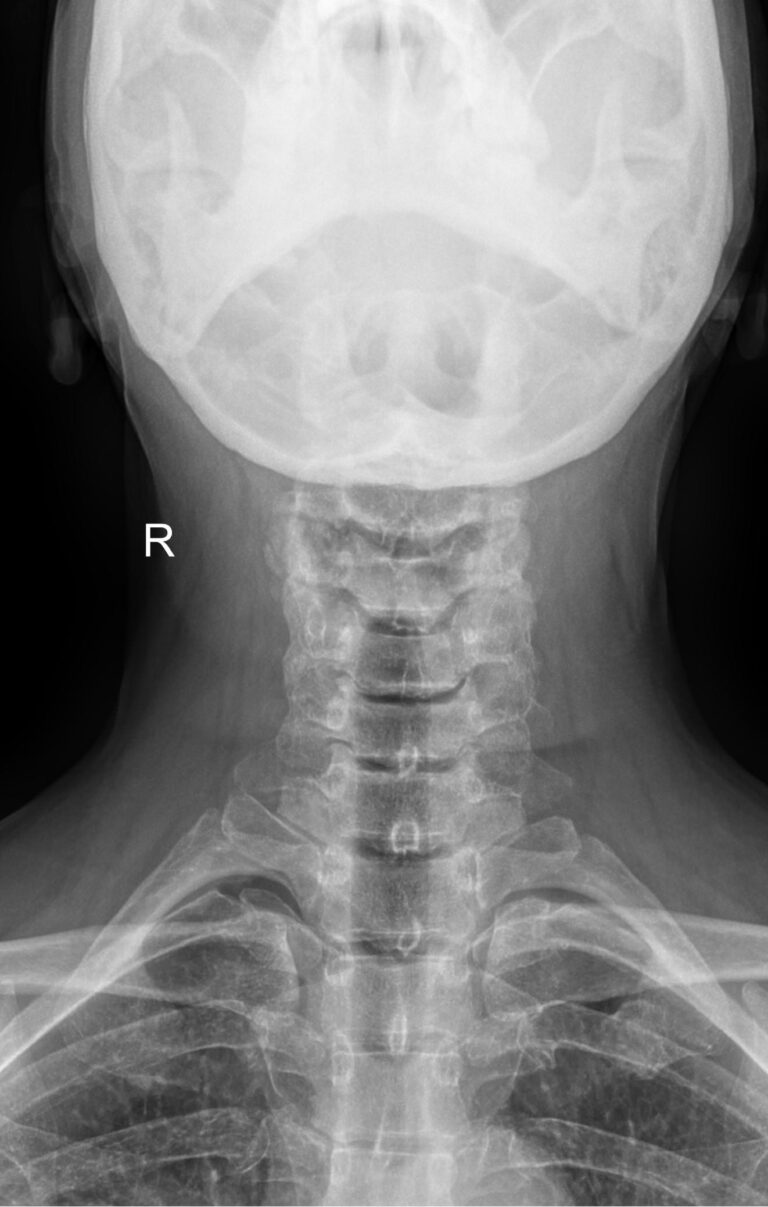

Как и другие кости, шейные позвонки отлично визуализируются с помощью рентгена. На снимках отчетливо видны признаки острых и хронических патологий, а часть врожденных аномалий обнаруживается случайно именно на рентгенограммах. В снимок попадают средние и нижние шейные, а также 2-3 верхних грудных позвонка. Для исследования двух верхних позвонков требуется специальная  проекция ― «через открытый рот».

Снимки могут быть назначены в 2 и более проекциях, которые указаны в направлении:

• Прямой ― лежа на спине с чуть запрокинутой головой;

• Боковой ― чаще стоя или сидя боком к пластине детектора;

• Косой ― тоже стоя или сидя, повернувшись к пластине на 30-45о.